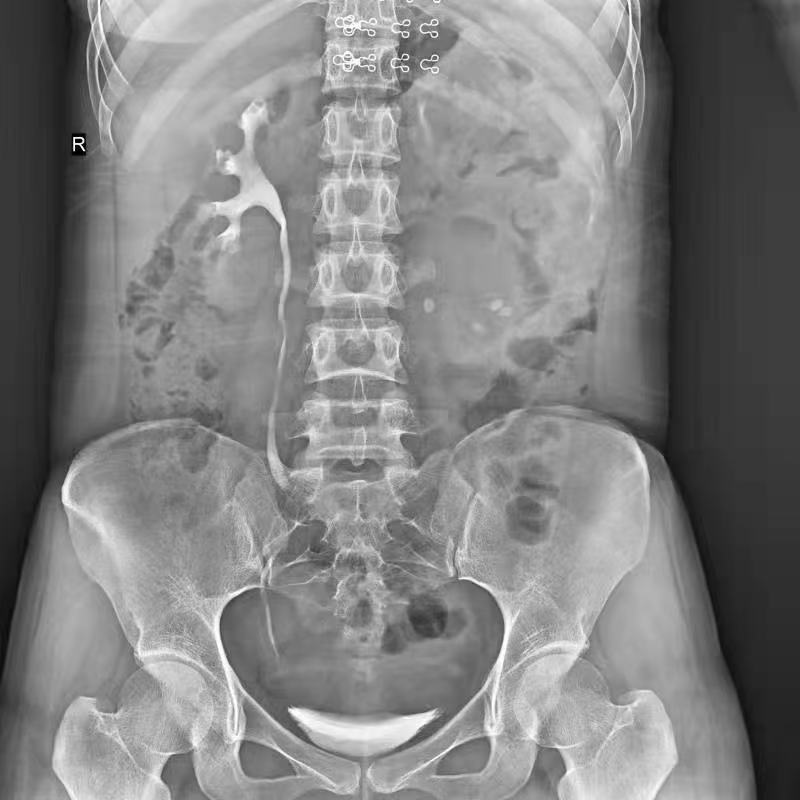

●呈現(xiàn)全下肢或全脊柱圖像

●在脊柱及下肢畸形矯正手術(shù)治療中,為術(shù)前方案制定和術(shù)后復(fù)查提供精準(zhǔn)測(cè)量

●有效解決傳統(tǒng)X光片不能一次成像問(wèn)題,為患者提供更加優(yōu)質(zhì)的醫(yī)療服務(wù)

點(diǎn)片裝置可實(shí)現(xiàn)大范圍縱向移動(dòng),高效完成各部位、全身拼接等檢查需求